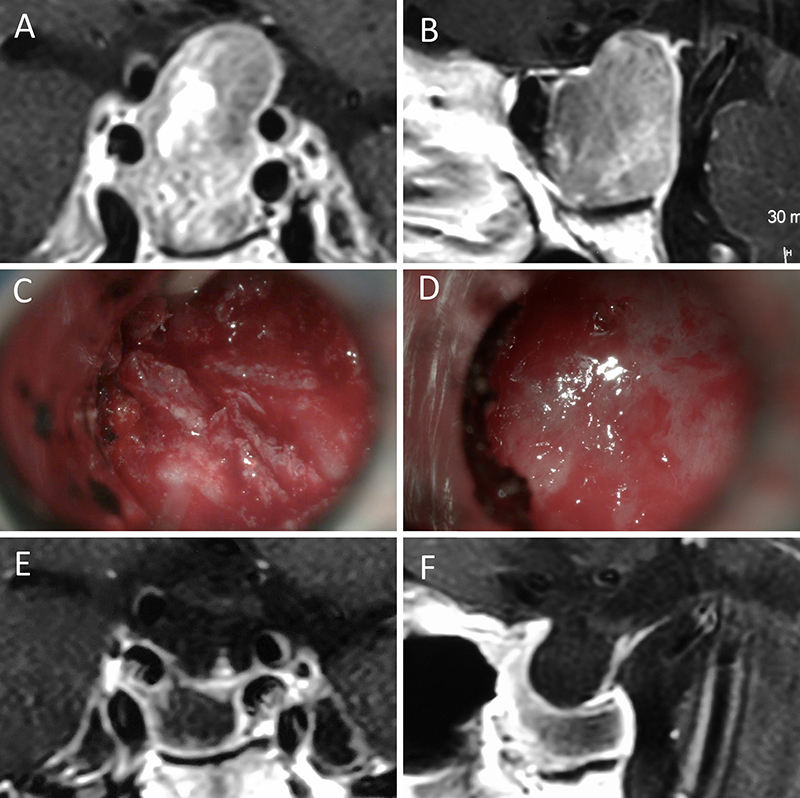

Figura 2: Macroadenoma no funcionante en mujer de 31 años. La paciente presentó en el preoperatorio déficit visual que mejoró tras la cirugía. A-B: RM preoperatoria; C-D: intraoperatorio; E-F: RM postoperatoria.